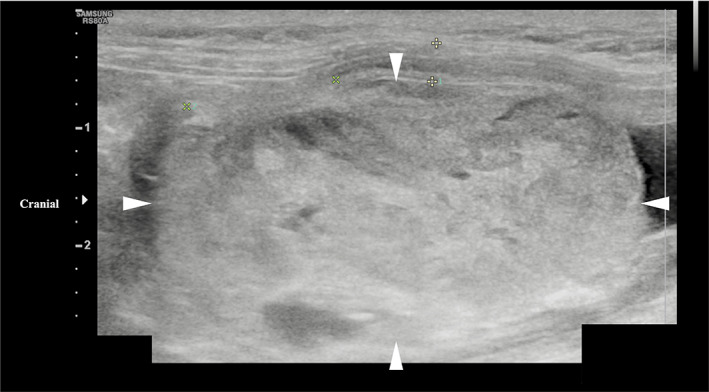

Abdominal ultrasound examination identified a smoothly marginated rounded mass within the bladder, measuring 4.1 × 2.2 cm and occupying 80% of the lumen (Figure 1). It had multiple irregular anechoic regions and moderate vascular supply. At the left cranial aspect of the bladder the mass appeared confluent with the bladder wall over an area of 13 mm. This region had a focal loss of layering, and the outer margin of the bladder wall was moderately irregular. A small volume of urine was observed at the bladder neck with a moderate volume of dependent echogenic non‐shadowing sediment. A urine sample was obtained by urethral catheterization and a sample of the mass obtained by catheter suction. No other abnormalities were noted. Urine cytology identified moderate pyuria with bacteriuria and hematuria. Urine aerobic and anaerobic bacterial culture and antimicrobial sensitivity indicated a urinary tract infection with Streptococcus lutetiensis, sensitive to penicillin, ampicillin, and chloramphenicol. Cytology of the mass identified low numbers of epithelial cells with minimal atypia, but overall was inconclusive because of the low number of nucleated cells. Based on imaging features such as the smooth luminal surface of the mass and irregularity of the serosal margin, a smooth muscle tumor such as a leiomyoma or leiomyosarcoma was considered; other differential diagnoses included transitional cell carcinoma, rhabdomyosarcoma, fibrosarcoma or lymphoma.

FIGURE 1.

Longitudinal ultrasound image of a urinary bladder hemangiosarcoma in a cat (margins of mass highlighted by arrowheads). The image shows a smoothly marginated, heterogenous mass originating from the left cranial bladder wall and occupying approximately 80% of the bladder lumen.